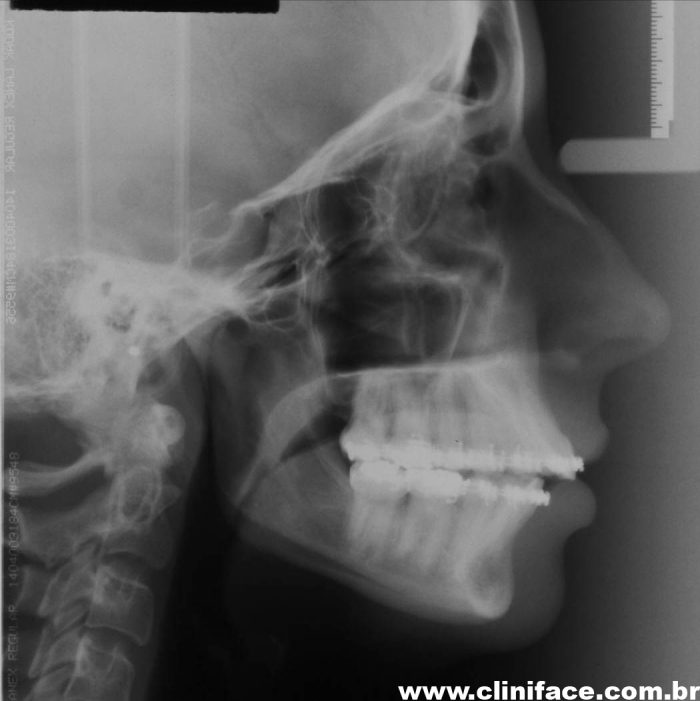

Teleradiografia inicial